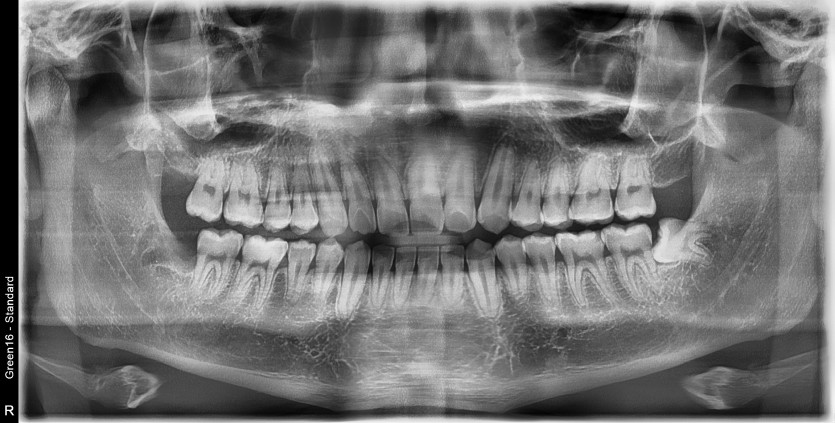

#48 사랑니 발치

구강 외과 전문의가 당일 발치했습니다.